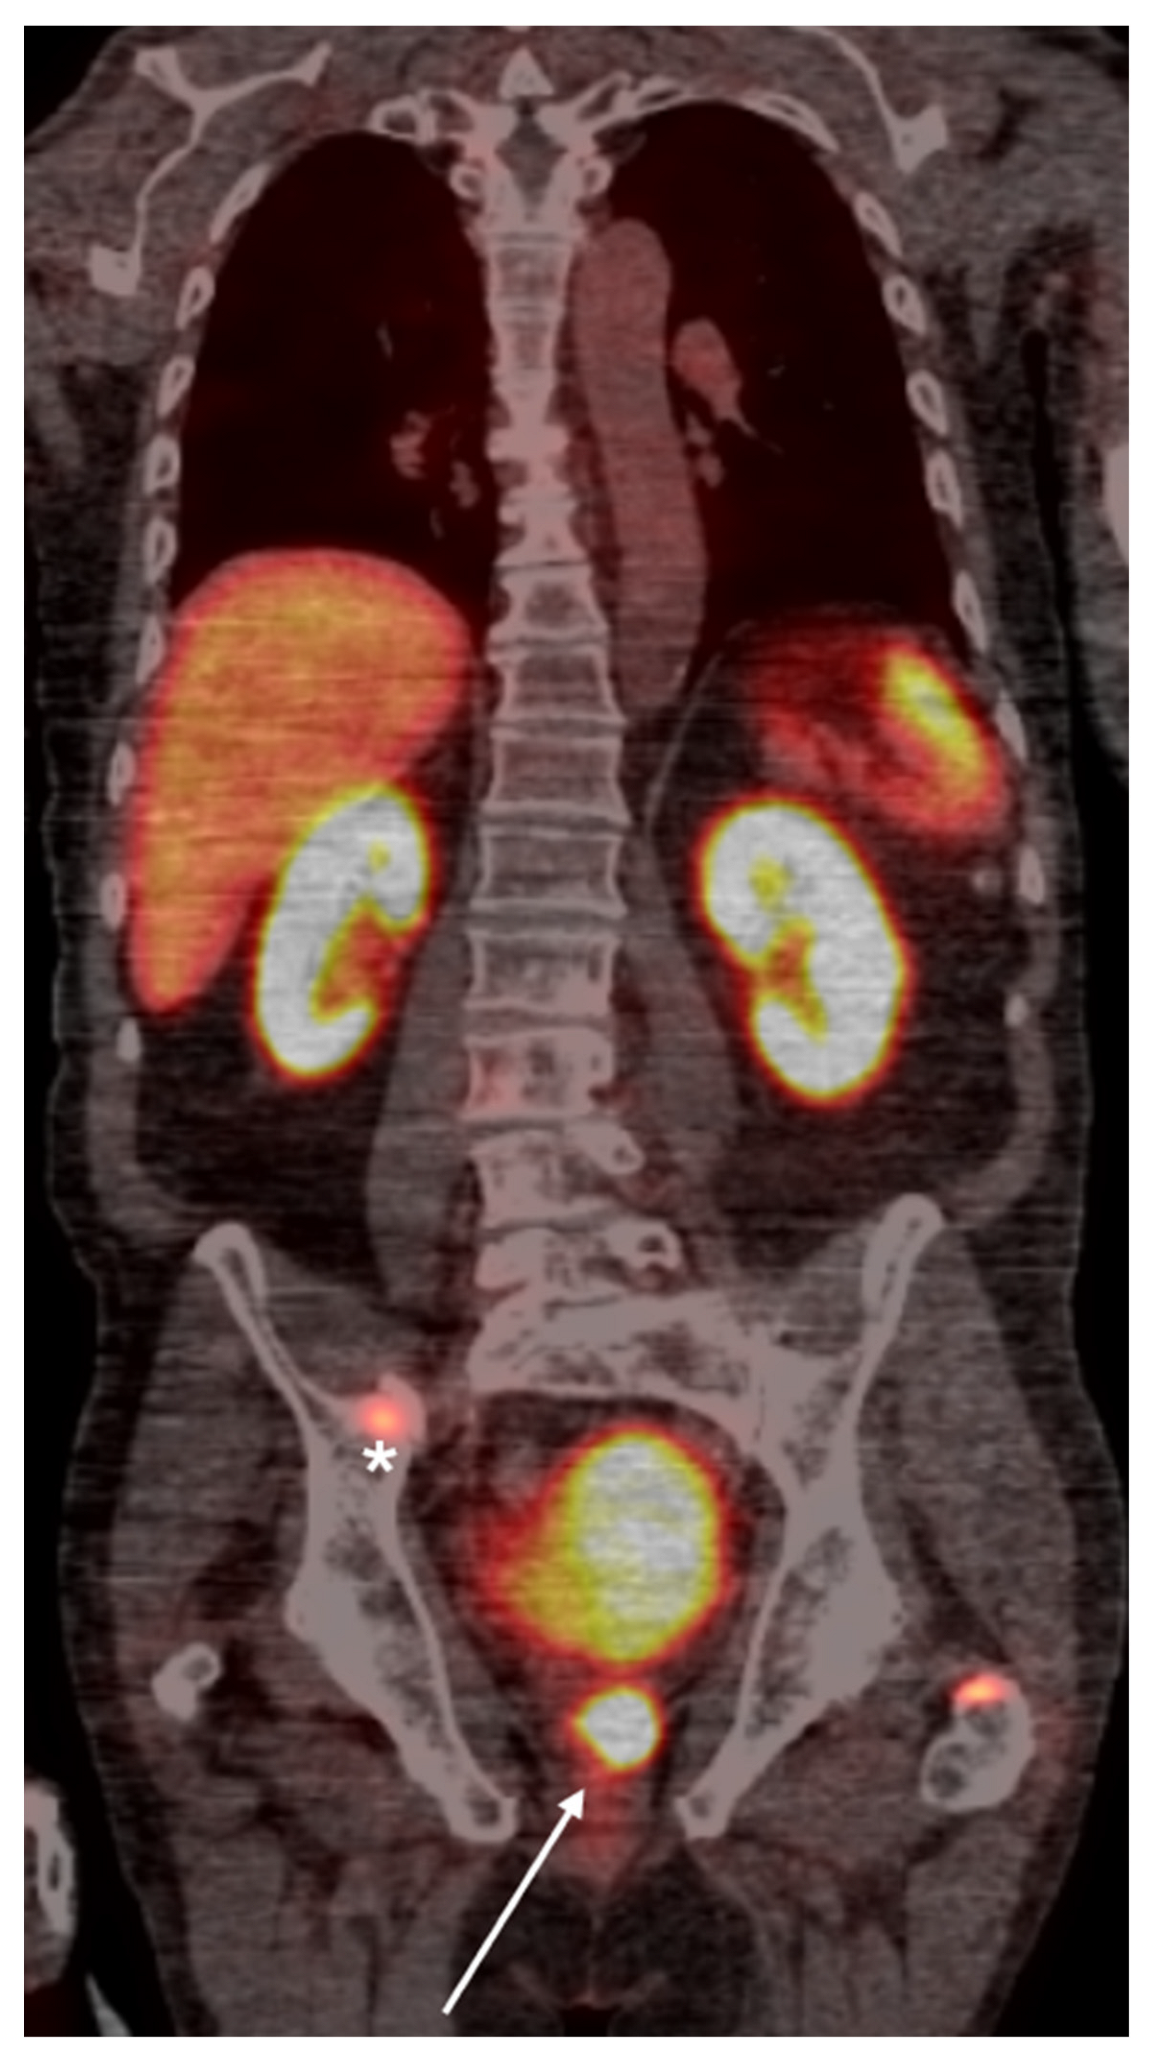

4. PSMA PET Imaging

- Adnan, A.; Basu, S. PSMA Receptor-Based PET-CT: The Basics and Current Status in Clinical and Research Applications. Diagnostics 2023, 13, 158. [Google Scholar] [CrossRef]

- Roberts, M.J.; Maurer, T.; Perera, M.; Eiber, M.; Hope, T.A.; Ost, P.; Siva, S.; Hofman, M.S.; Murphy, D.G.; Emmett, L.; et al. Using PSMA imaging for prognostication in localized and advanced prostate cancer. Nat. Rev. Urol. 2023, 20, 23–47. [Google Scholar] [CrossRef]

- Jochumsen, M.R.; Bouchelouche, K. PSMA PET/CT imaging in prostate cancer: Impact on clinical management and patient outcomes. Clin. Nucl. Med. 2024, 49, 1–10. [Google Scholar]

- Houshmand, S.; Salavati, A.; Solnes, L.B. Clinical applications of PSMA PET in prostate cancer management. PET Clin. 2023, 18, 1–18. [Google Scholar]

- Fendler, W.P.; Calais, J.; Eiber, M.; Flavell, R.R.; Rettig, M.B. PSMA PET for prostate cancer imaging: The current status and future directions. J. Nucl. Med. 2023, 64, 28–37. [Google Scholar]

- Plouznikof, N.; Garcia, C.; Artigas, C.; Entezari, K.; Flamen, P. Heterogeneity of 68Ga-PSMA PET/CT uptake in fibrous dysplasia. Clin. Nucl. Med. 2019, 44, E593–E594. [Google Scholar] [CrossRef]

- Smith, S.E.; Murphey, M.D.; Motamedi, K.; Mulligan, M.E.; Resnik, C.S.; Gannon, F.H. From the archives of the AFIP. Radiologic spectrum of Paget disease of bone and its complications with pathologic correlation. Radiographics 2002, 22, 1191–1216. [Google Scholar] [CrossRef]

- Zarzour, J.G.; Galgano, S.; McConathy, J.; Thomas, J.V.; Rais-Bahrami, S. Lymph node imaging in initial staging of prostate cancer: An overview and update. World J Radiol. 2017;9(10):389-399. [CrossRef]